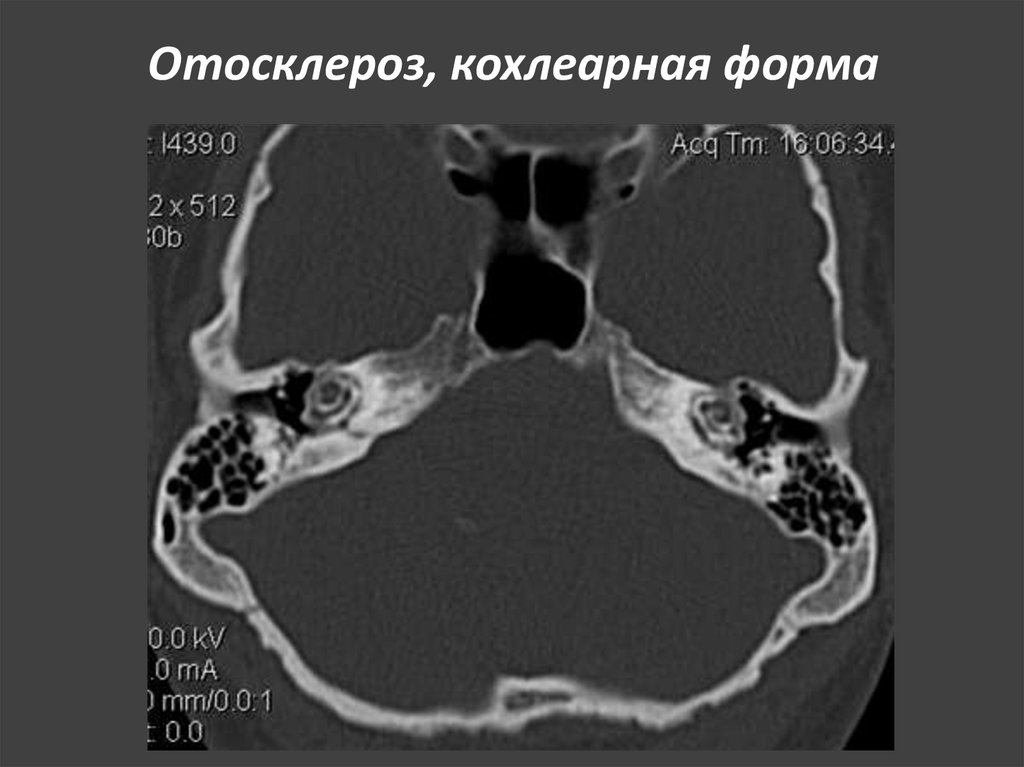

165. Отосклероз, кохлеарная форма

ОСЛОЖНЕНИЯ: